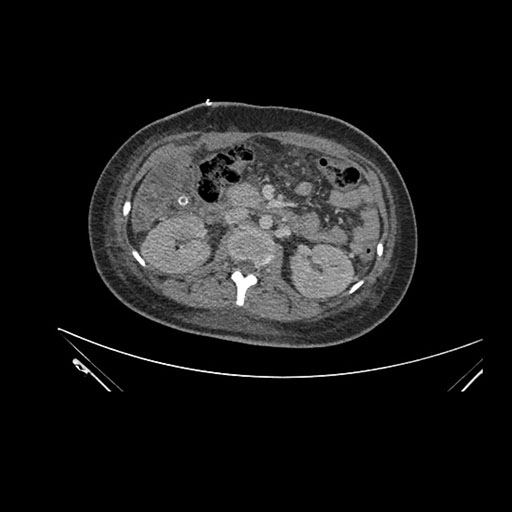

Imaging Analysis

Look through the patient's CT scan to identify any areas of concern for the necessary procedure.

Axial Arterial

Based on initial findings, which issue(s) would you be most concerned about?